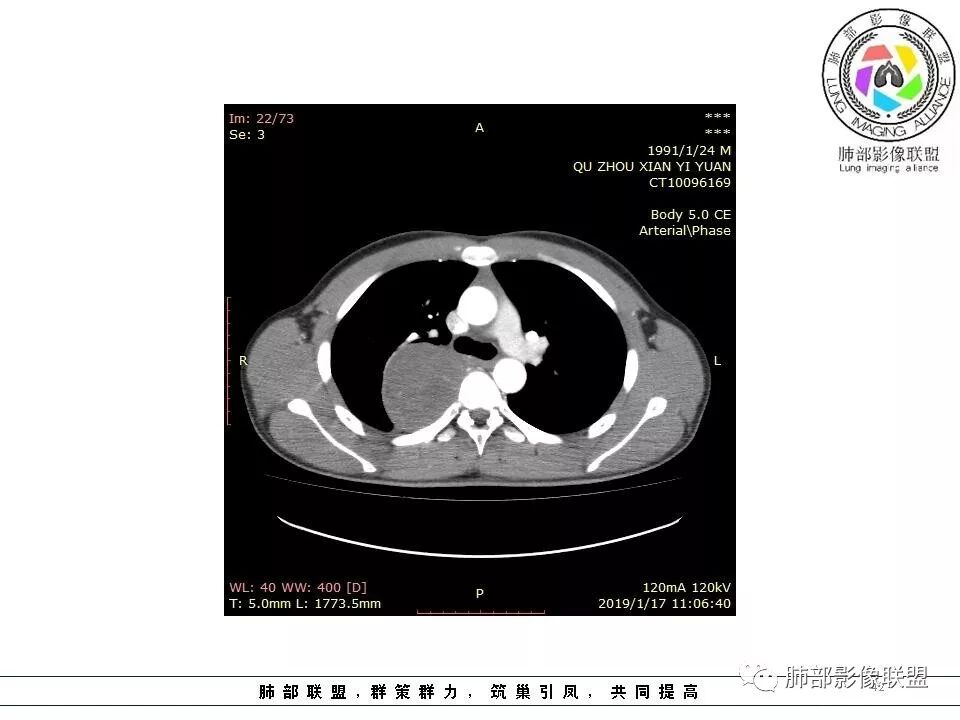

右后纵膈脊柱旁软组织占位,形态规则类圆,边缘光整,肺组织受压,胸膜尾,肋间动脉供血。中度不均匀延迟强化。

右后纵膈脊柱旁软组织占位,边界清晰,光整,肺组织受压。胸膜被掀起,肋间动脉供血,中度不均匀延迟强化。考虑神经鞘瘤,不除外纤维瘤

右后纵膈脊柱旁软组织影,与纵隔结构分界不清,形态规则类圆,边缘光整,肺组织受压,胸膜尾,肋间动脉供血。肺动脉推移,中度不均匀延迟强化。考虑神经来源,神经鞘瘤,神经纤维瘤二者不易鉴别。

青年男性,间断胸痛;右侧脊柱旁可见一类圆形软组织密度影,密度欠均匀,增强扫描呈轻中度持续强化,邻近肺组织及肺动脉推移,可见肋间动脉供血,部分胸膜下脂肪可见,部分层面似见与右侧椎间孔相连。考虑后纵隔神经源性肿瘤。

1.右上胸内脊柱旁类圆形肿块,质地似乎比较坚实,密度稍显不均,但未显示明确的坏死。

如此密度形态的病灶位于肺边缘首先应当想到孤立性纤维瘤,可相邻胸膜未见明显的异常强化和胸膜方向延伸。

2.肋间动脉病供血也提示肿块来自后纵隔?